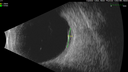

72 year old female Starting 7 weeks ago there was a vision change in the right eye. The patient was diagnosed with CSR. She might have preceding COVID. She was not on steroids. She had a virus for 2 months - starting mid January. She has been feeling OK for 2 weeks. She had a strange rash on her head and is using steroids but that started after the vision loss. She has a history of skin melanoma on the inside of her arm removed in 2015-6. She had a carcinoid tumor at age 43 and then again in 2014. That was surgically removed. Medical Hx: Hypertension, Systemic (Controlled). Arrhythmias. Atrial Fibrillation. Carcinoid Tumor (Removed). Skin Cancer (Melanoma). Hashimoto's Disease (went away had covid in January 2024. Herpes. Surgical Hx: Gallbladder (Onset: 2013). Moh's Surgery. Systemic Meds: metoprolol tartrate 25 MG (metoprolol succinate 23.75 MG) Oral Tablet. Telmisartantelmisartan tablet 40mg. Flecainide Acetate, 100 mg oral tablet. Eliquis bid. MICARDIS. Aspirin 81 mg qweek. ZYRTEC qhs. benadryl qhs. VA OD: sc20/100-1 VA OS: sc20/40-2 IOP: TP: OD:15 OS:16

Serous Macular Detachment from Small Choroidal Melanoma49 views72 year old female misdiagnosed as CSR who had small choroidal melanoms.00000